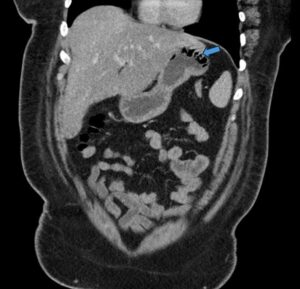

Gastric Emphysema. Coronal CT, annotated. JETem 2024

Gastric Emphysema. Coronal CT annotated. JETem 2024